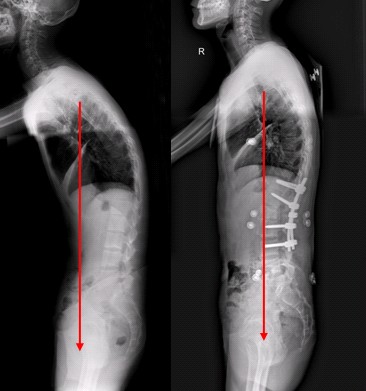

强直性脊柱炎的症状早期常有下背痛和晨起僵硬、活动后减轻,并可伴有低热、乏力、食欲减退、消瘦等症状。开始时疼痛为间歇性,数月数年后发展为持续性疼痛,以后炎性疼痛消失,脊柱由下而上部分或全部强直,出现驼背畸形。

(1)脊柱改变:病变发展到中、晚期可见。